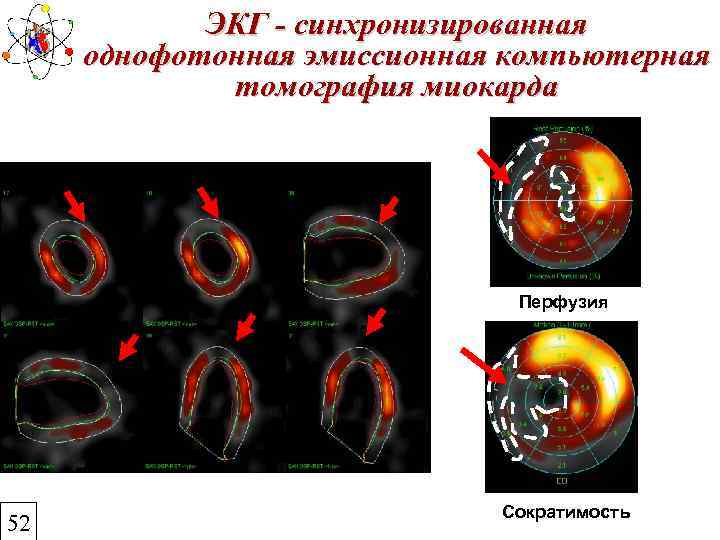

ЭКГ - синхронизированная однофотонная эмиссионная компьютерная томография миокарда Перфузия 52 Сократимость

ЭКГ - синхронизированная однофотонная эмиссионная компьютерная томография миокарда Перфузия 52 Сократимость